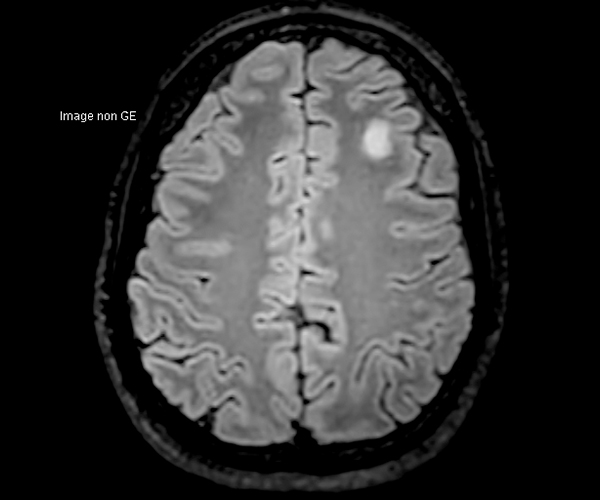

Concernant l’imagerie cérébrale, l’IRM 3T permet d’augmenter la sensibilité de détection de lésions ischémiques aiguës de petite taille, notamment chez les patients adressés pour accident ischémique transitoire (accident vasculaire cérébral), grâce à la séquence de diffusion dont le signal et la résolution sont augmentés.

L’amélioration de la résolution spatiale s’applique à l’exploration morphologique des hippocampes dans le diagnostic de la maladie d’Alzheimer, à la détection de petites lésions de sclérose en plaques ou de métastases, à l’étude fine du cortex dans les épilepsies.